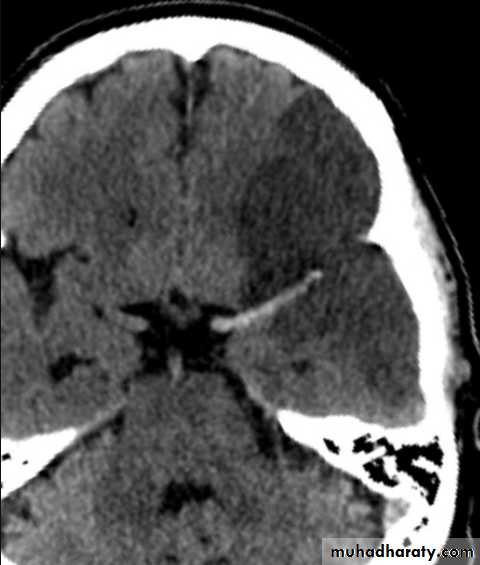

Acute infarction

History: sudden onset of hemiplegia , with slurred speech .

CT features:

Wedge shape area of hypo density involve the tributaries of anterior , middle or posterior cerebral arteries , ( i.e. priato frontal &priato occipital area )

Shift of the midline to the other side .

Compression of the ipsi lateral aspect of the regional ventricle by the edema

Dense middle artery sign

* wedge shape hypo density area.* Shifting of the midline & frontal horn